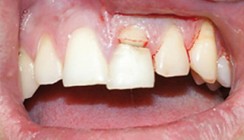

Eine Woche später wurde der Zahn 11 in der Kinderzahnarztpraxis von Dr. Christina Masuck behandelt. Der Zahn reagierte weiterhin normal positiv auf Kältetests. Beim Entfernen der provisorischen Abdeckung der pulpanahen Bereiche stellte sich eine minimale Eröffnung der Pulpa dar. Es wurde mit H2O2 (3%) desinfiziert und die „P“ mit Calxyl (Kerr Life) sowie einer Unterfüllung (Vitrebond) abgedeckt. Anschließend wurde der Zahn mit Komposit dentinadhäsiv aufgebaut (Abb. 11). Mit dem Ergebnis der ästhetisch und funktionell wiederhergestellten Zahnreihe waren sowohl der Patient als auch seine Eltern sehr zufrieden (Abb. 12). Auch die Kontrolle acht Monate nach dem Frontzahntrauma zeigte einen beschwerdefreien Patienten. Alle Zähne waren perkussionsunempfindlich. Der replantierte, endodontisch versorgte Zahn 21 war sowohl klinisch als auch röntgenologisch völlig unauffällig. Das Röntgenbild zeigte keine periradikulären Veränderungen und gab kein Anzeichen für interne oder externe Wurzelresorptionen (Abb. 13).